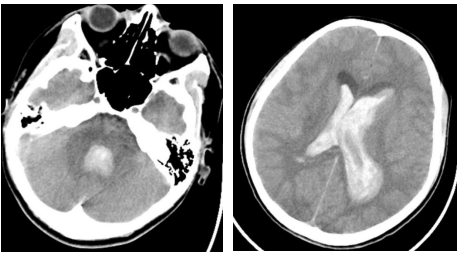

▲头颅CT显示脑室出血,脑室铸型,梗阻性脑积水

8月14日深夜,120救护车的警笛声撕破长空。一名年仅14岁的患儿被送到了北京市垂杨柳医院急诊科。同行的患儿家属表示,患儿一家是外地来京旅游的,没有既往病史。当天患儿在酒店洗澡时突发头痛伴呕吐,并很快昏迷。急诊科医师在接诊后迅速启动绿色通道,神经外科值班医生段练接到电话后迅速赶到急诊会诊。经头颅CT检查显示,患儿脑室出血,脑室铸型,梗阻性脑积水。在检查期间,患儿病情进一步恶化,出现四肢抽搐,去脑强直发作,且呼吸不规则,血氧低。一场由神经外科主导,急诊科、第一手术区、麻醉科、导管室、重症医学科等多学科共同协作的“生死争夺战”就此展开。